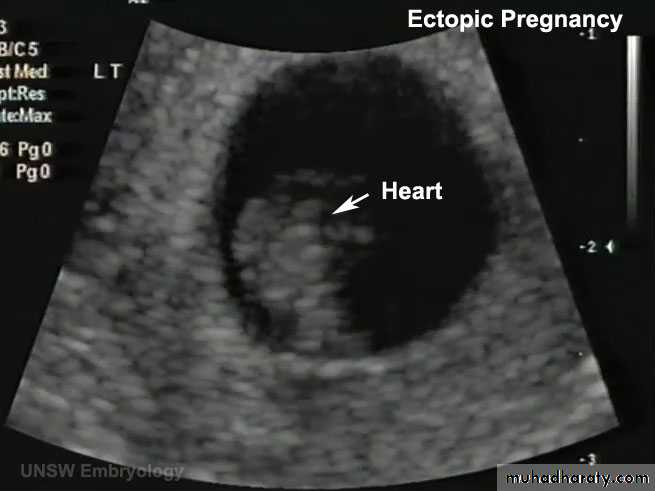

ECTOPIC PREG (EXTRAUTERINE PREG):

- 95% …. Uterine tube… and mostly in the ampula

In most ectopic preg the embryo dies in the second month of gestation… causing sever hrg and abd painMost abnormal blastocyst would not have any signs of preg bec of inferior trophoblast… no hCG … corp luteum not persist

• A 23-year-old woman consulted her physician about severe right lower abdominal pain. She said that she had missed two menstrual periods. A diagnosis of ectopic pregnancy was made.

What techniques might be used to enable this diagnosis?

What is the most likely site of the extrauterine gestation (pregnancy)?

How do you think the physician would likely treat the condition?